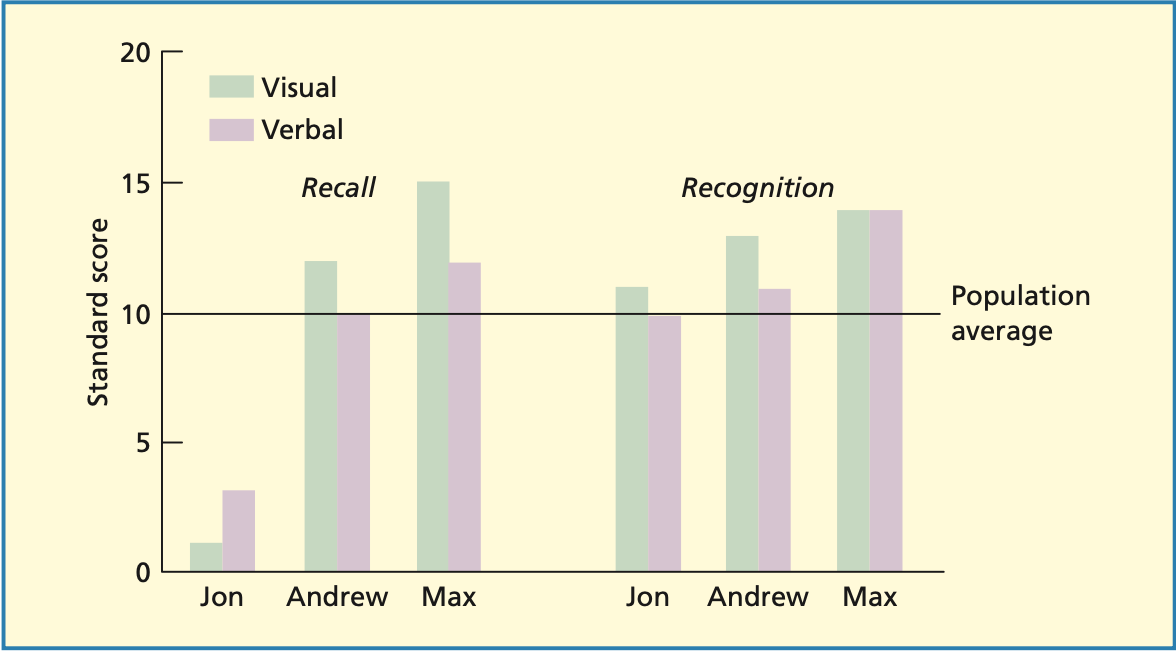

Fallbeispiel: Jon

Amnesie seit Kindheit

Guter Wortschatz & hoher IQ

Entgegen früherer Annahmen:

Gute Leistung bei Wiedererkennung

Schlechte Leistung beim Abruf

Normalerweise Abruf und Wiedererkennung betroffen